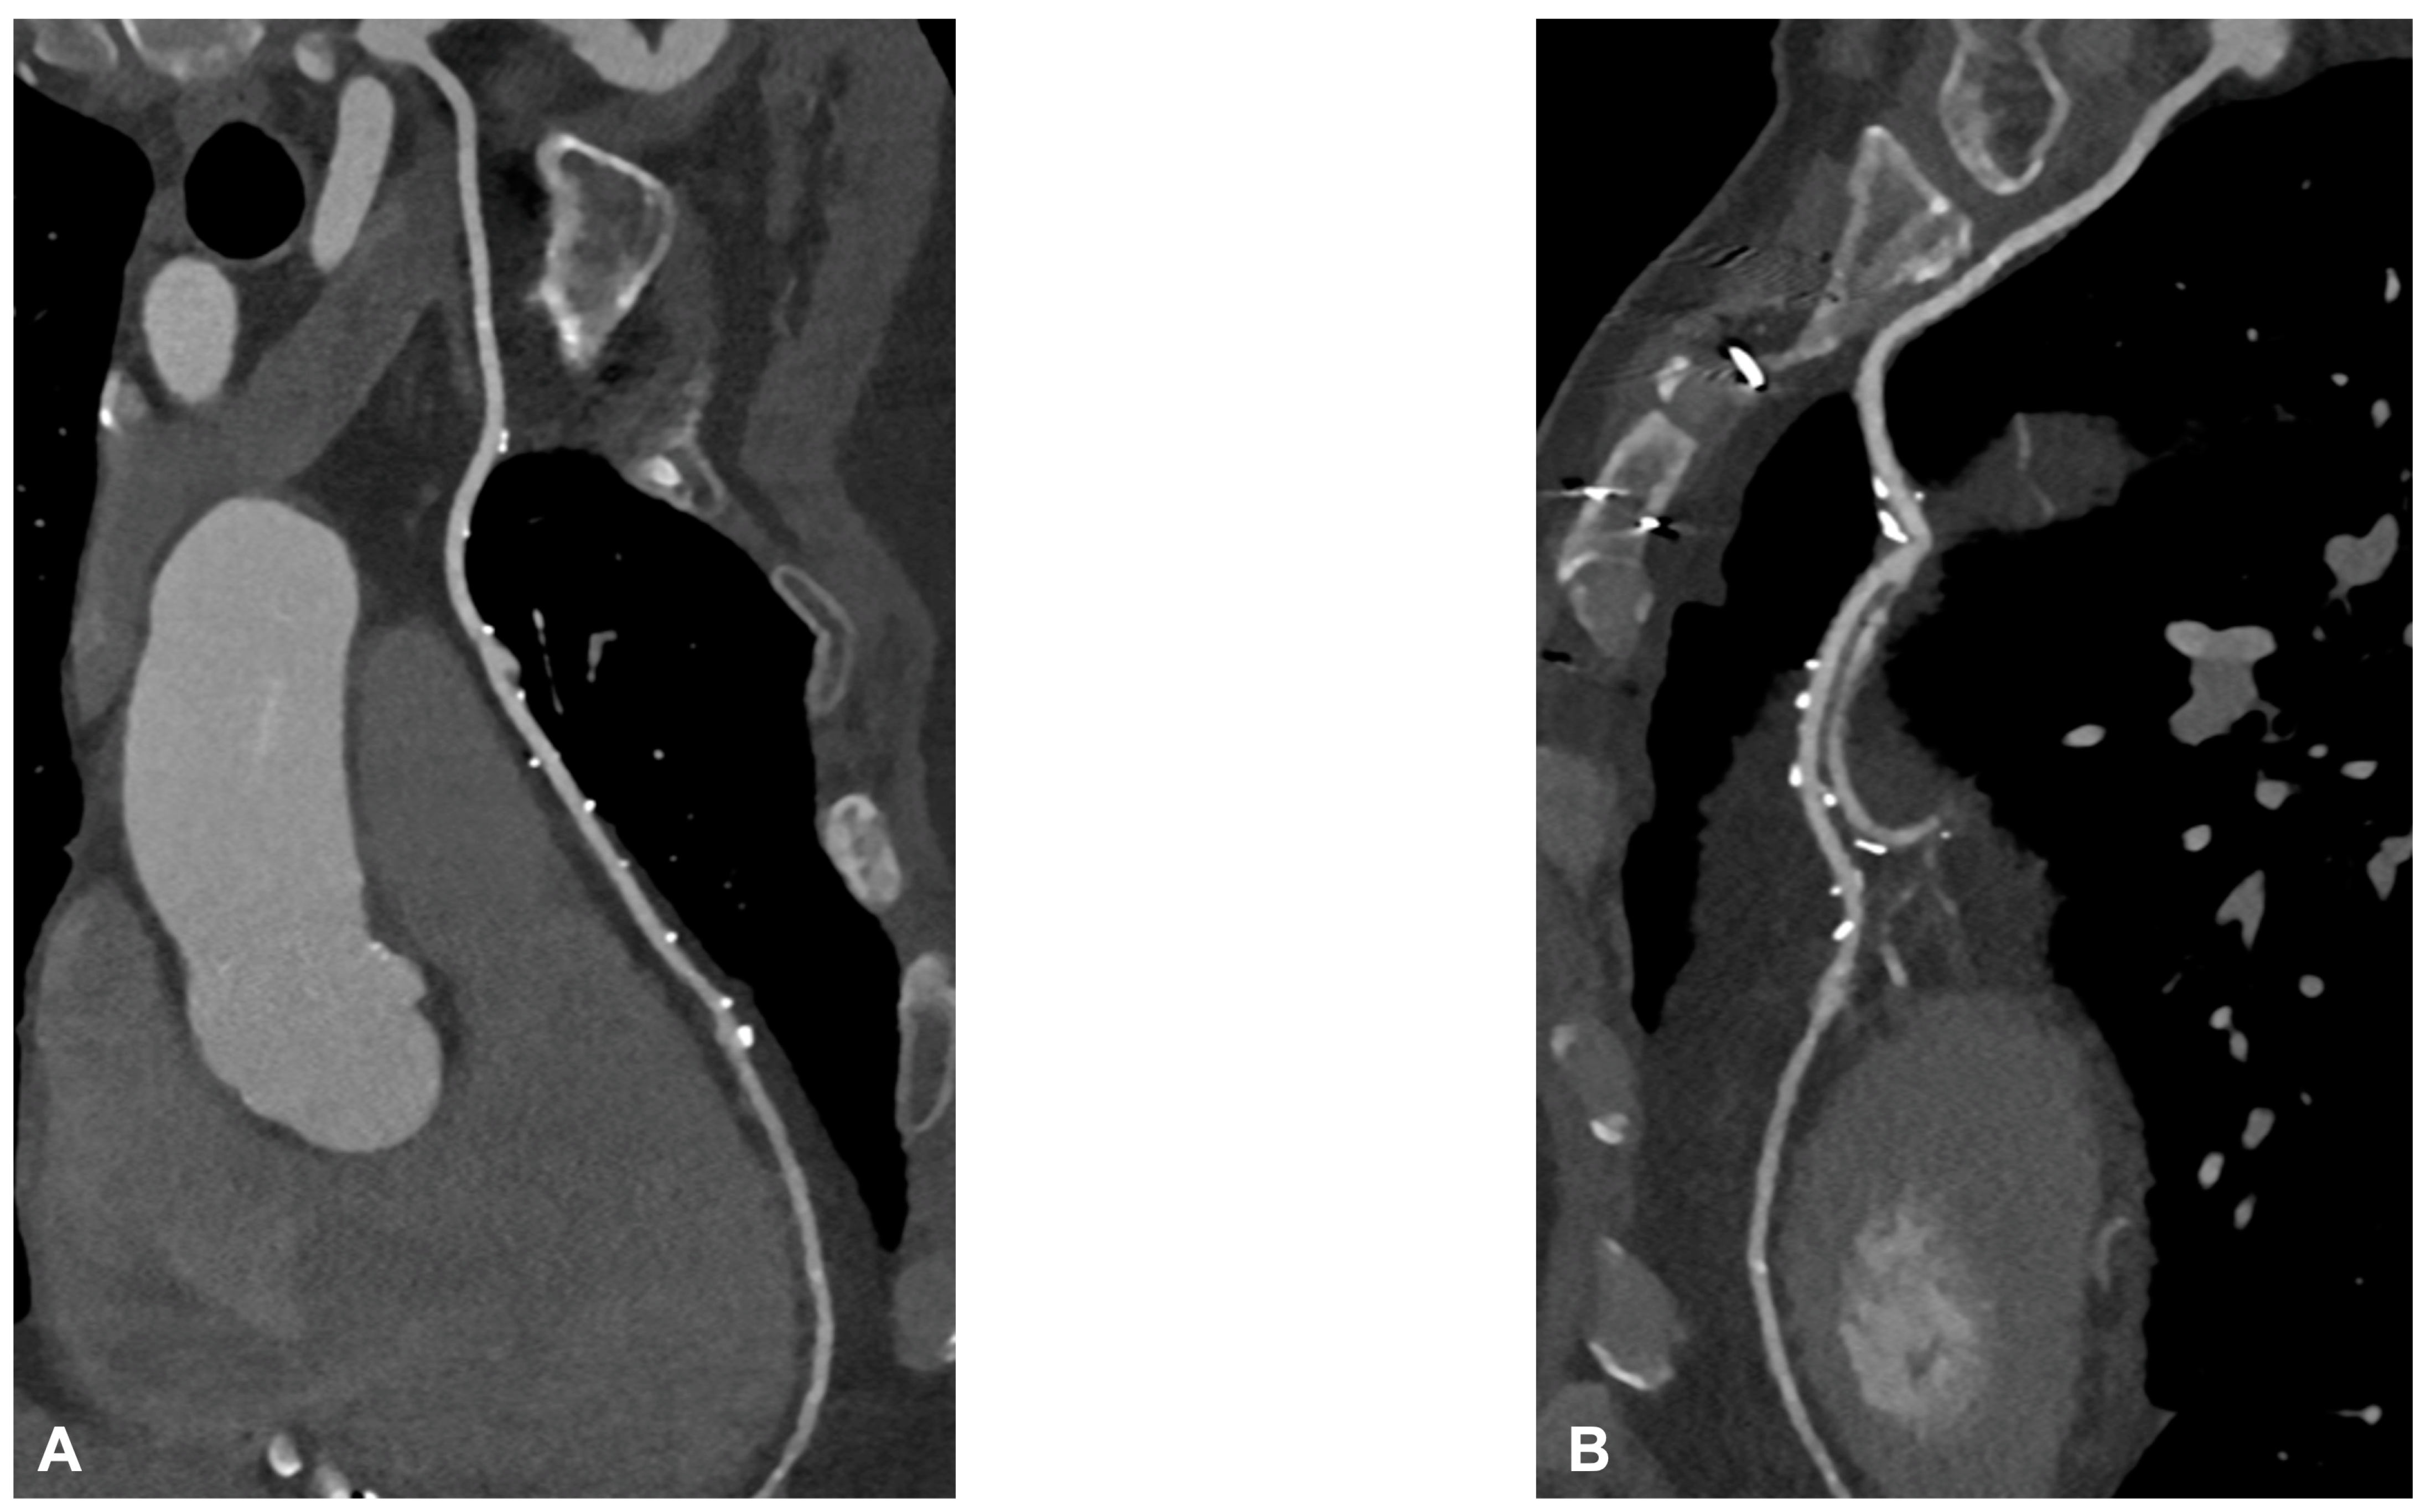

Graft failure remains a significant concern, with reported occurrence rates ranging from 3% to 10%. Data from the literature underlined that the occlusion of the internal mammary artery within the initial year following surgery has a prevalence of 5.7% in men and 3.4% in women [20]. The saphenous vein graft showed a lower patency rate compared with the internal mammary artery. Typically, saphenous grafts exhibit occlusion rates of 12% within the first six months after surgery, which increases to 25% after five years. Subsequently, the patency rate declines to 50% at 15 years or more post-surgery [21]. Angina may be associated with graft failure and occlusion, but within the first five years following surgery, in 50% of cases, angina is linked to the progression of native coronary artery obstruction [22]. Graft failure can lead to several issues, such as refractory angina, myocardial ischemia, arrhythmias, low cardiac output, and fatal cardiac failure, emphasizing the importance of ensuring graft patency during and after surgery to prevent complications. To address this issue, several techniques have been provided to evaluate graft patency after coronary artery bypass graft (CABG) surgery [23]. Coronary angiography is currently the gold standard for assessing the status of CABG; however, this is an invasive method, and it has a certain number of complications. Engagement and visualization of venous and arterial bypass grafts frequently prolong procedure time and are associated with larger contrast use, increased radiation exposure, and higher risk of embolization and dissection during catheter manipulation [11]. Therefore, there is a need for a noninvasive method with good diagnostic accuracy for the follow-up of CABG patients. The 2010 multi-societal Appropriate Use Criteria (AUC) defined coronary Computed Tomography Angiography (CTA) as “Appropriate” for the evaluation of CABG patency in patients with ischemic symptoms [24]. Surgical grafts are ideal vessels to be assessed by CCTA because of their large diameter, low incidence of severe calcifications, and less influence by heart movements when compared to native coronary arteries. Figure 5A,B and Figure 6 show some examples of the CABG assessment by CCTA. In Figure 5, the left internal mammary artery was used, and an anastomosis with the native left coronary artery was created. Figure 5 highlights the feasibility of CCTA in CABG patients, with good diagnostic accuracy of grafts that appear free from plaque proliferation. The distal part of native coronary arteries appears patent with a good opacification by contrast medium. Figure 6 shows an occluded saphenous vein graft previously treated with stenting. In a study that included symptomatic patients who had undergone CABG surgery approximately 10 ± 5 years prior and underwent CCTA, Malagutti et al. demonstrated that CCTA exhibited a sensitivity of 100% and a specificity of 98.3% in detecting graft patency when compared to ICA. Additionally, their findings indicated that overestimation of obstruction was more likely in native coronary arteries, particularly in the presence of calcification [9]. In a meta-analysis by Barbero et al., which focused on patients experiencing angina or suspected symptoms of myocardial infarction following CABG, the study examined the sensitivity and specificity of 64-slice CT in detecting graft occlusion and stenosis exceeding 50%. The sensitivity and specificity for identifying any coronary artery bypass graft with stenosis greater than 50% were found to be 0.98 (95% CI: 0.97–0.99) and 0.98 (95% CI: 0.96–0.98), respectively. These observations remained consistent regardless of age and were applicable to both arterial and venous conduits, resulting in an area under the curve of 0.99 were independent of age and consistent in both arterial and venous conduits resulting in an area under the curve of 0.99 [10]. A comparative study between CCTA and ICA by Weustink et al. involving symptomatic post-CABG patients concluded that CCTA demonstrated a diagnostic accuracy of 100% in identifying or ruling out significant stenosis in grafts. The specificity, sensitivity, PPV, and NPV all yielded 100% accuracy in the detection of significant stenosis. As a result, they concluded that CCTA was valuable and exhibited high diagnostic accuracy for identifying post-CABG significant stenosis or graft occlusion [11]. Although CCTA is highly accurate for bypass grafts, the evaluation of native coronary arteries in patients with prior CABG can be challenging due to the diffuse and severe nature of underlying coronary artery disease. For example, the sensitivity for detection of stenosis ≥ 50% in recipient and nongrafted vessels is typically lower (83–90%) in patients with CABG than in patients without prior CABG. However, there are limitations associated with CCTA, which encompass its incapability to identify stenosis or blockages in heavily calcified coronary arteries, the tendency to overestimate stenosis due to calcification, challenges in visualizing distal anastomosis, image quality issues stemming from artifacts caused by hemostatic metal clips, difficulties when patients cannot hold their breath, rapid heart rate, atrial fibrillation, and residual coronary motion [25]. However, the novel whole-heart coverage CT scanners allow the avoidance of some of the above-mentioned limitations: a study by Mushtaq S et al. showed that CCTA successfully interpreted 100% of the bypass grafts. When compared to ICA, CCTA exhibited the ability to identify occlusion and significant stenosis in all CABG segments, with sensitivity, specificity, PPV, and NPV of 100% each for the grafts. With these results, the study concluded that last-generation whole-heart coverage CT scanners can assess bypass grafts with very good interpretability and a lower level of radiation [12].

Figure 5.

In (A,B), two multiplanar reconstructed images of the left internal mammary artery CABG on the left anterior descending coronary artery. There are no signs of degenerative disease with the patency of grafts.

Figure 6.

An occluded saphenous vein graft to the right coronary artery. The graft was previously treated with a stent, which appears occluded.